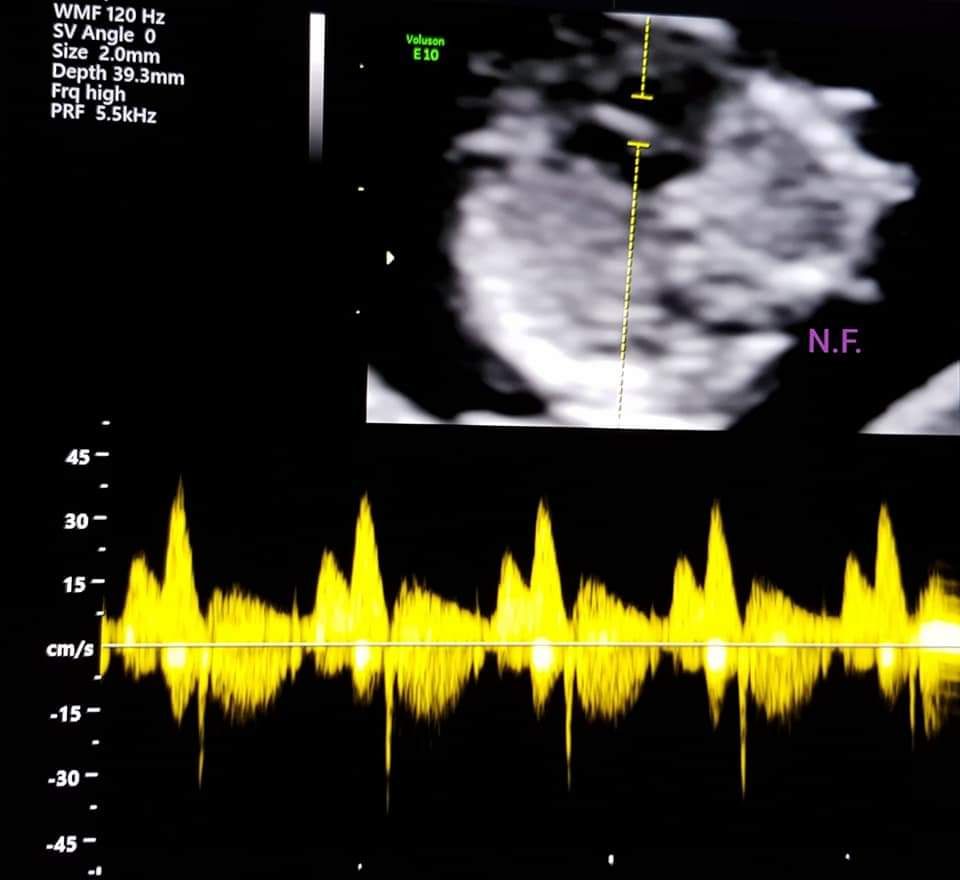

Foto e video

• Studio Ginecologico- Dott.ssa Nadia Fichera ecocardiografia fetale  •